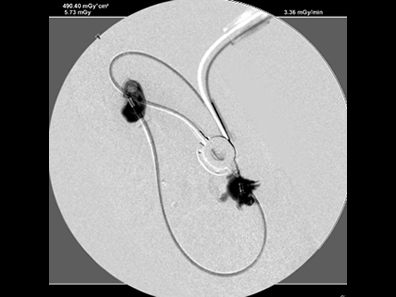

造影で漏れがないか何度も確認

必ず透視下にて漏れがないか何度も確認をします。 透視をしないとシステムや装着部分からの漏れが確認されたり、トラブルが考えられます。

実際、他院で装着して漏れがあるなどの相談をうけることがしばしばあります。

透視下にて実施すれば適切な位置に装着できます。

綺麗につければ感染や漏れもほとんどなく、経過はとても良好です。

SUBシステムを設置しました。

漏れを確認して終了となりました。